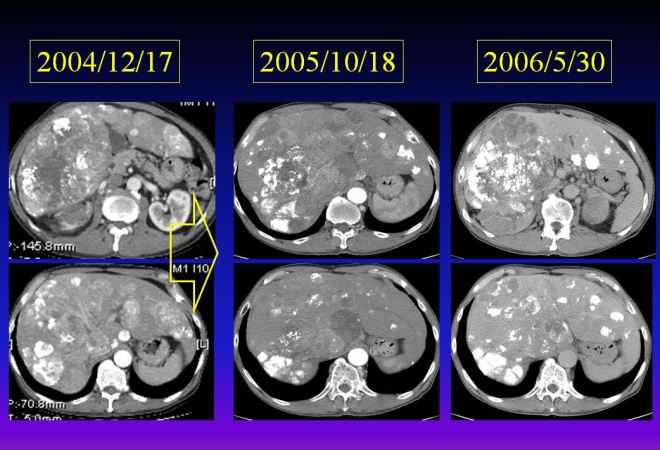

다음은 색전술 1년 뒤인 2005년도 CT 사진이다.

간에 있던 암들이 현저히 소실이 되어서 암이 보이는 부분만 수록하였으므로 위와 level이 조금 다르다. 하지만 이전에 보이던 간 좌엽의 우들두들하던 경계면의 간이 약간 재생되어서 자라면서 매끈해졌고 리피오돌 uptake 된 부분이 현저히 줄어들었다. 다음은 2004년과 약 8개월 뒤인 2005년도의 비교 사진이다. 우리는 두 사진을 비교해 볼 때 색전술이 매우 잘 반응을 했음을 알 수 있다.

이후 내원 당시 2006년도 사진과 비교해 보겠다.

이 사진을 비교해 보면 level들이 약간씩 다르지만 가장 중점적으로 암이 보이는 부분을 담았다. 아래쪽사진에서는 2005년 10월보다 2006년 5월이 다소 더 증가한 듯이 보인다. 하지만 main인 위쪽 사진은 많이 종양이 감소되었고 2004년도와 비교해 보면 간 좌엽은 경화로 보이던 면도 매우 매끄러워져 있어서 간경화도 소실된 분위기이고 암도 잘 멈추어 있다고 볼 수 있다.